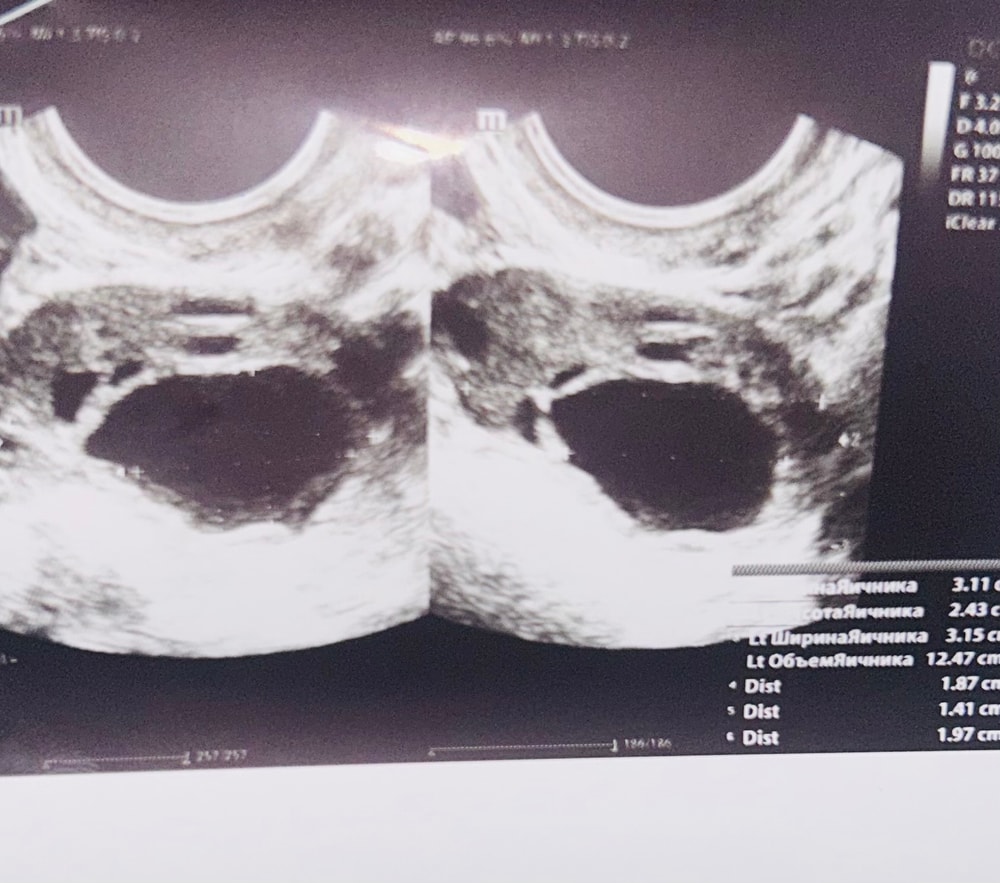

УЗИ 23 дц, анэхогенное образование

УЗИДобрый день! Под вопросом был СПКЯ, тк циклы были до 17 дней. Вдруг - 23 дц и все еще не заканчивается, вот узи: фото внутри поста

собственно, вопрос: что за образование? киста или желтое тело?

Размеры: 43х28×33 мм. Контуры: четкие,Форма матки грушевидная

Правый яичник:

Визуализация: удовлетворительная. Топография: не изменена. Размеры: 31х24х32 мм, объем 12,5 см3. Форма: правильная. Контуры: четкие. Капсула: не визуализируется. Структура: с множественными мелкими анэхогенными включениямиКороткий текст. Дополнительно: содержит анэхогенное образование неправильной формы 19×14×20 мм с прерывистым кровотоком, 10 мелких фолликулов